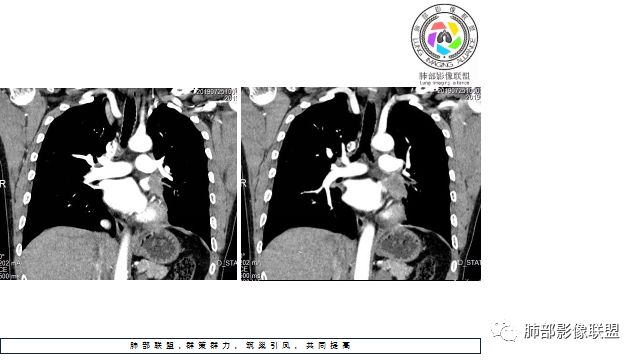

4.病灶内有肺动脉走形,血管局部受压,未见破坏,病灶乏血供,呈血管包埋或血管造影征;侵袭性力强及破坏力弱、血管漂浮都符合SCLC,所以鳞癌的可能性也不大。

5.左肺门块影或淋巴结肿大,竭力挤兑肺门血管结构,呈冰冻肺门;有时候SCLC可以单独呈现冰冻肺门,而没有没有冰冻纵隔。

中年男性,咳嗽痰中带血10个月,左肺下叶靠近肺门巨大肿块,有分叶,支气管受压截断,左肺动脉及肺静脉均受侵破坏,肺门同侧淋巴结肿大,病灶中度不均质强化,同侧少量胸腔积液。考虑恶性肿瘤,小细胞或腺癌可能性大。

中年男性,左肺下叶团块,边界尚清,分叶明显,左肺下叶支气管阻塞,远端阻塞性肺炎不显著,增强扫描肿块明显强化,尚均匀,坏死不明显,内见部分强化血管影,包绕肺动脉并侵蚀破坏,局部伸入左主支气管与主动脉间隙,左侧肾上腺区似见肿块,NSE略高,左侧胸腔积液。综合考虑左肺下叶占位,考虑恶性,小细胞肺癌肺癌可能性大,鉴别腺癌,类癌及淋巴瘤。建议支气管镜检查或穿刺活检。